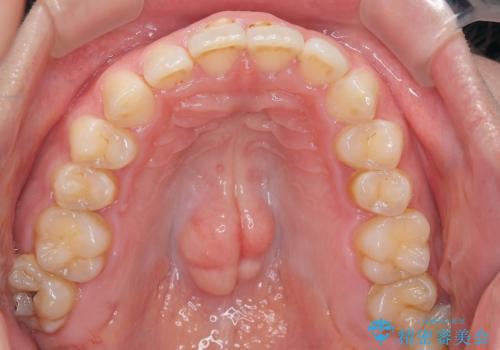

噛み合わせをよくするために、ワイヤー矯正とインビザライン矯正のどちらの期間も必要な箇所にゴム掛けを行いながら治療を行いました。

下の前歯のがたつき改善にはIPR(歯と歯の間を削る処置)を行いました。

ゴム掛けを頑張っていただいたので、噛みあわせも改善され綺麗な歯並びになりました。